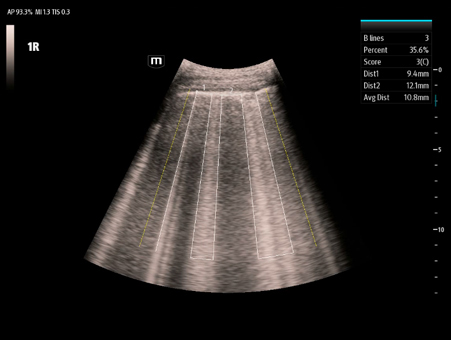

MindrayŌĆśs critical Ultrasound solutions drive improvements in care quality. Integrating advanced hemodynamic Ultrasound features, we can guarantee the highest standard of clinical care. The unique interoperability of Ultrasound and Vital sign data, we can provide comprehensive patient status data, to help inform clinical decisions, enhance clinical efficiency and, ultimately, improve patient outcomes.